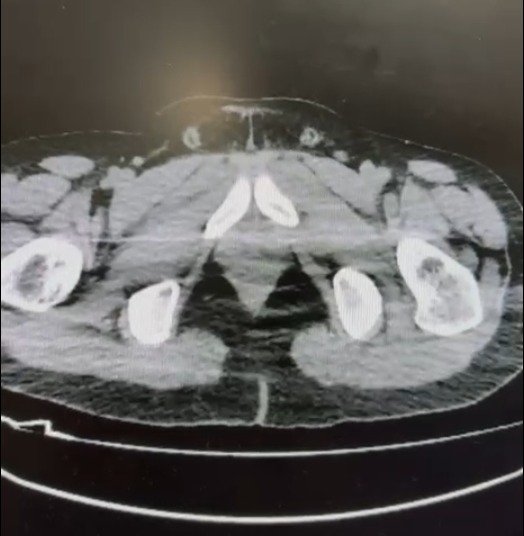

Nevşehir Cumhuriyet Başsavcılığı koordinesinde yürütülen çalışmalar kapsamında, S.B. ve O.R. isimli şahısların “yutma yöntemi” ile Nevşehir’e uyuşturucu madde sevk edeceği bilgisine ulaşıldı.

Şüphelilerin ikametlerinde ve kullandıkları araçlarda yapılan aramalarda;

- 101 kapsül halinde toplam 722 gram metamfetamin maddesi,